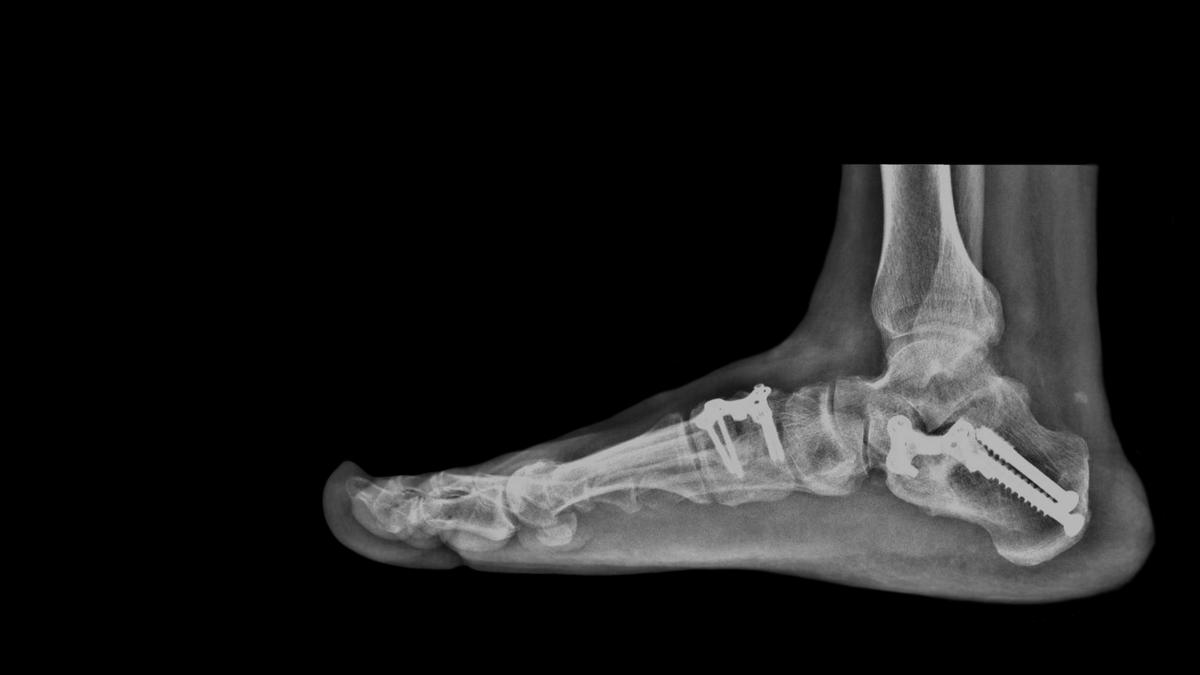

• Fixation: Metal screws, plates, or rods are used to hold the bones in place and maintain proper alignment during the healing process.

• Bone Preparation: The surfaces of the tibia (shinbone) and talus (ankle bone) are carefully prepared by removing the remaining cartilage, exposing healthy bone.

• Bone Alignment: The surgeon aligns the tibia and talus bones in the proper position, ensuring optimal contact and stability for fusion.